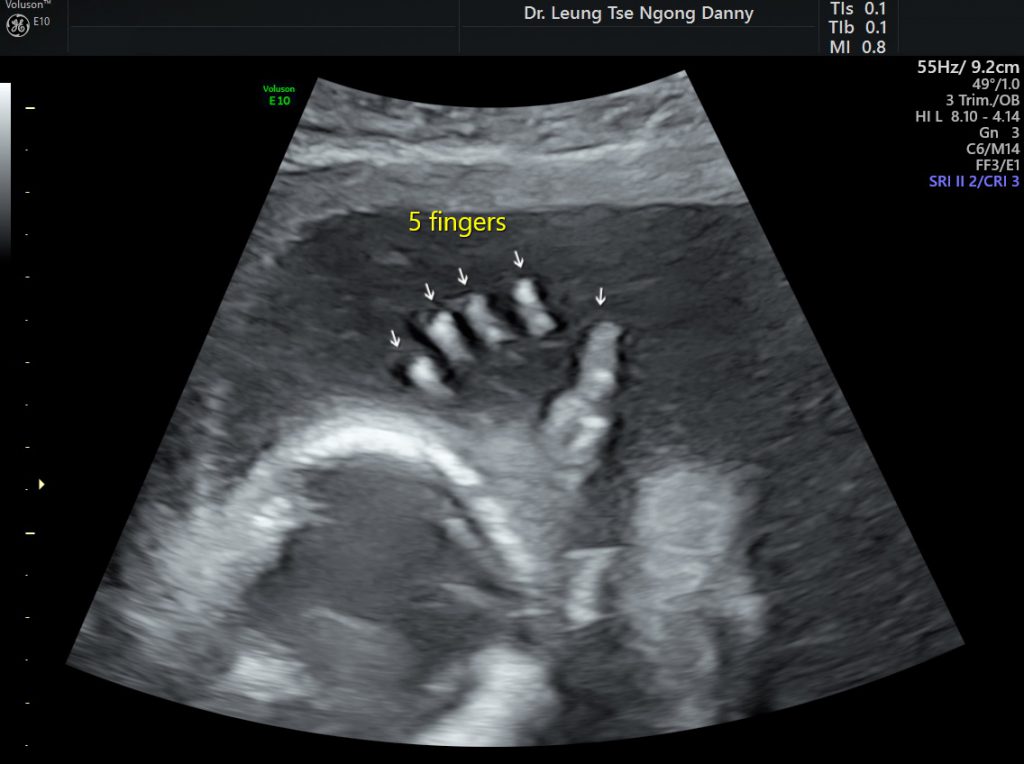

From hkog-info.com

Routine fetal morphology scan HKOGINFO Causes Of Fetal Finger Pads Another common finding is an abnormal. persistent fetal finger pads are a common and distinctive symptom of ks. Some people with kabuki syndrome have prominent pads on their fingertips. prominent finger pads are called fetal finger pads because they normally occur in human fetuses; Pads like this generally form in fetuses but are usually gone before birth. These. Causes Of Fetal Finger Pads.